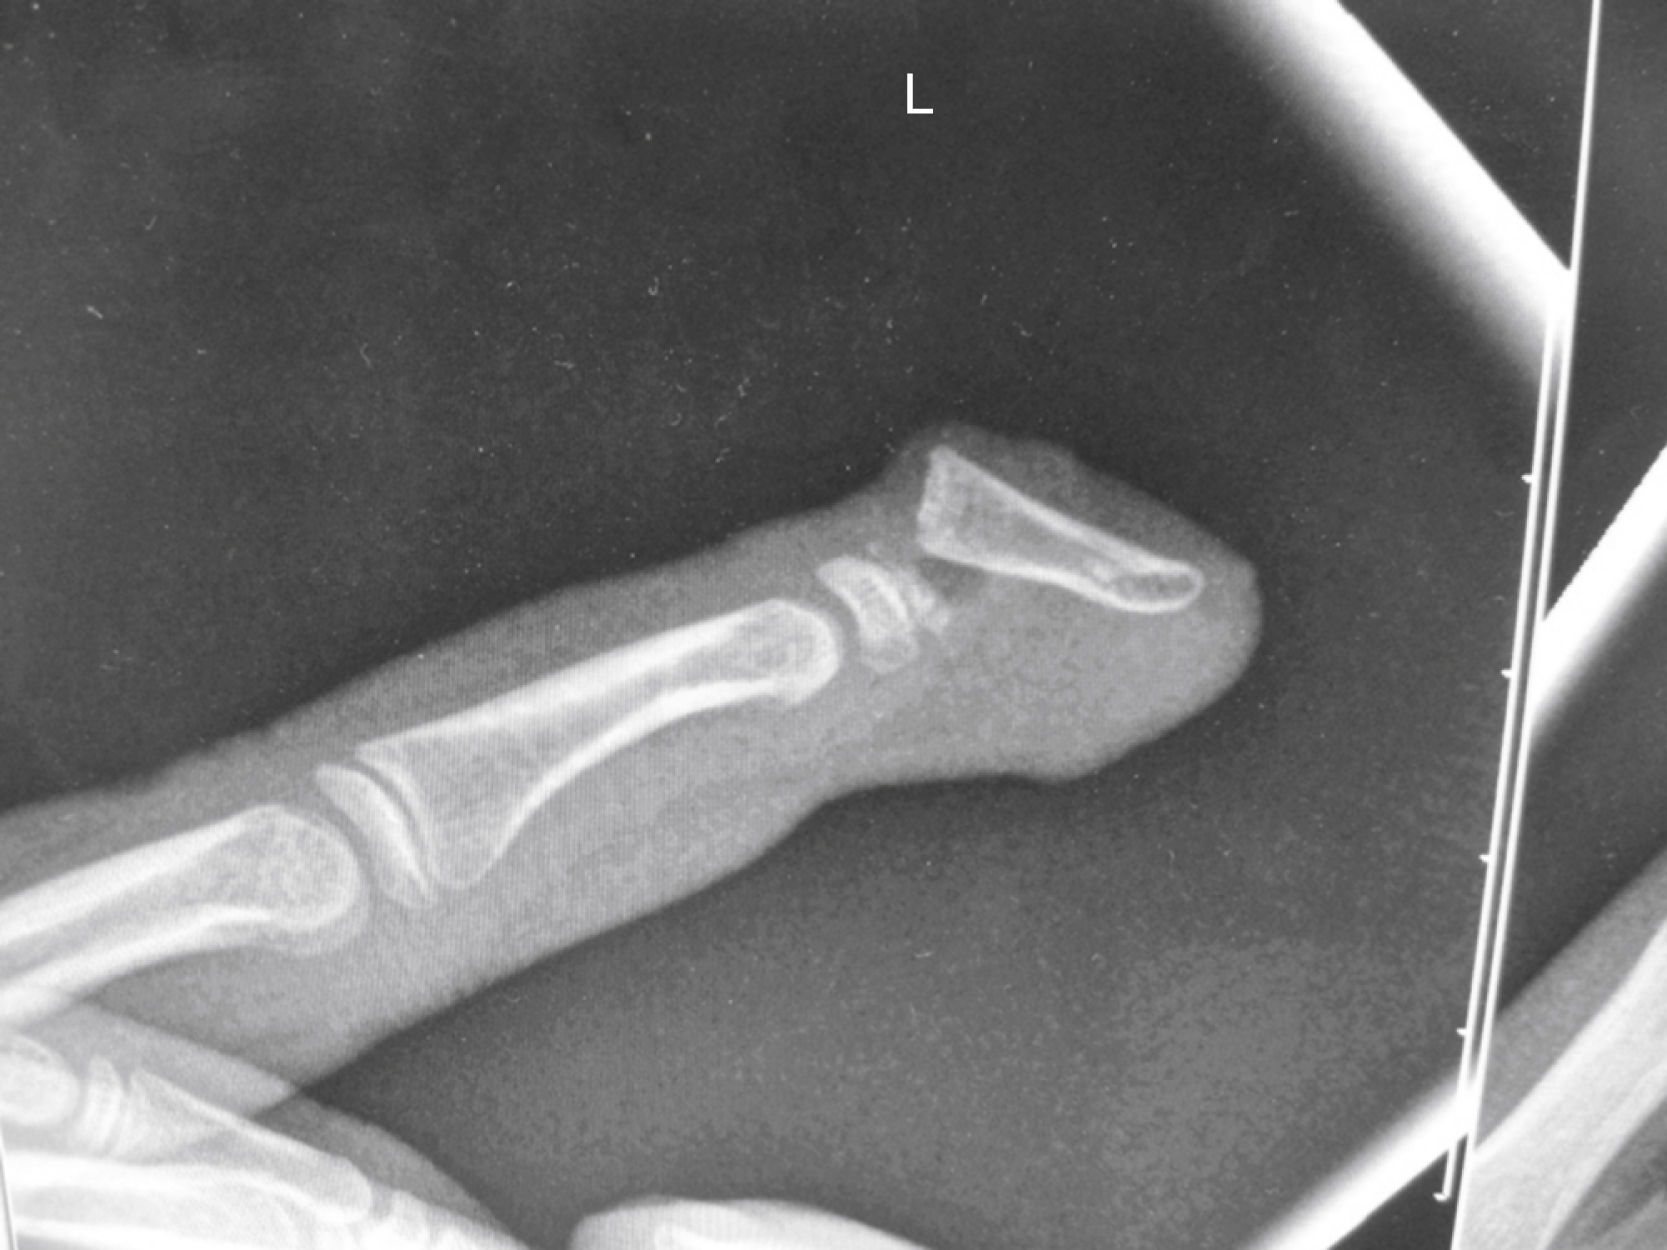

Crush distal phalanx fractures and nailbed injuries are the most common pediatric fracture. These occasionally need a Kirschner-wire (K-wire) or an orange needle to pin a larger distal fragment in place, but often the fragment is too small. A special type of nailbed injury is the Seymour fractures, which are displaced distal phalanx Salter I or II fractures, with avulsion of the proximal edge of the nail from the eponychial fold and the germinal matrix often interposed in the fracture itself ( Fig. 56.2 ). Accurate and timely debridement and repositioning of all tissues is therefore paramount to allow adequate growth of both digit and nail. The clinical presentation can be confused with a mallet finger (because the extensor tendon inserts itself in the epiphysis whilst the flexor tendon inserts itself in the metaphysis), but a true lateral X-ray and a thorough examination under anesthetic should reveal the injury.

Fractures through the neck of the phalanges are usually only found in children and mostly involve some unfortunate interface between fingers and doors. Al-Qattan divided them into three categories, which determined prognosis and treatment: type I fractures are undisplaced, type II fractures are displaced, but maintain some bone-to-bone contact, whilst type III fractures have no bone-to-bone contact. Type III is furthermore subdivided according to the location of the distal fragment, type IIID especially being associated with an avascular fingertip ( Fig. 56.3 ). Since the smallest displacement is poorly tolerated, all types apart from type I require open reduction and K-wiring, but have progressively worse prognoses.